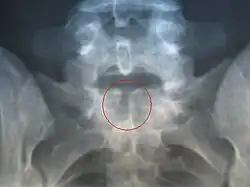

Spina bifida occulta

Часто эта форма называется «скрытое расщепление позвоночника», так как при этом спинной мозг и нервные корешки в норме, а также отсутствует дефект в области спины. Данная форма характеризуется лишь небольшим дефектом или щелью в позвонках, которые формируют позвоночный столб. Зачастую эта форма патологии настолько умеренно выражена, что не вызывает каких-либо беспокойств. При этом такие больные даже не знают о наличии у себя этого порока развития и узнают об этом лишь после рентгенографии. Чаще всего эта форма патологии возникает в пояснично-крестцовом отделе позвоночника. У 1 из 1000 больных могут отмечаться проблемы с функцией мочевого пузыря или кишечника, боли в спине, слабость мышц ног и сколиоз.